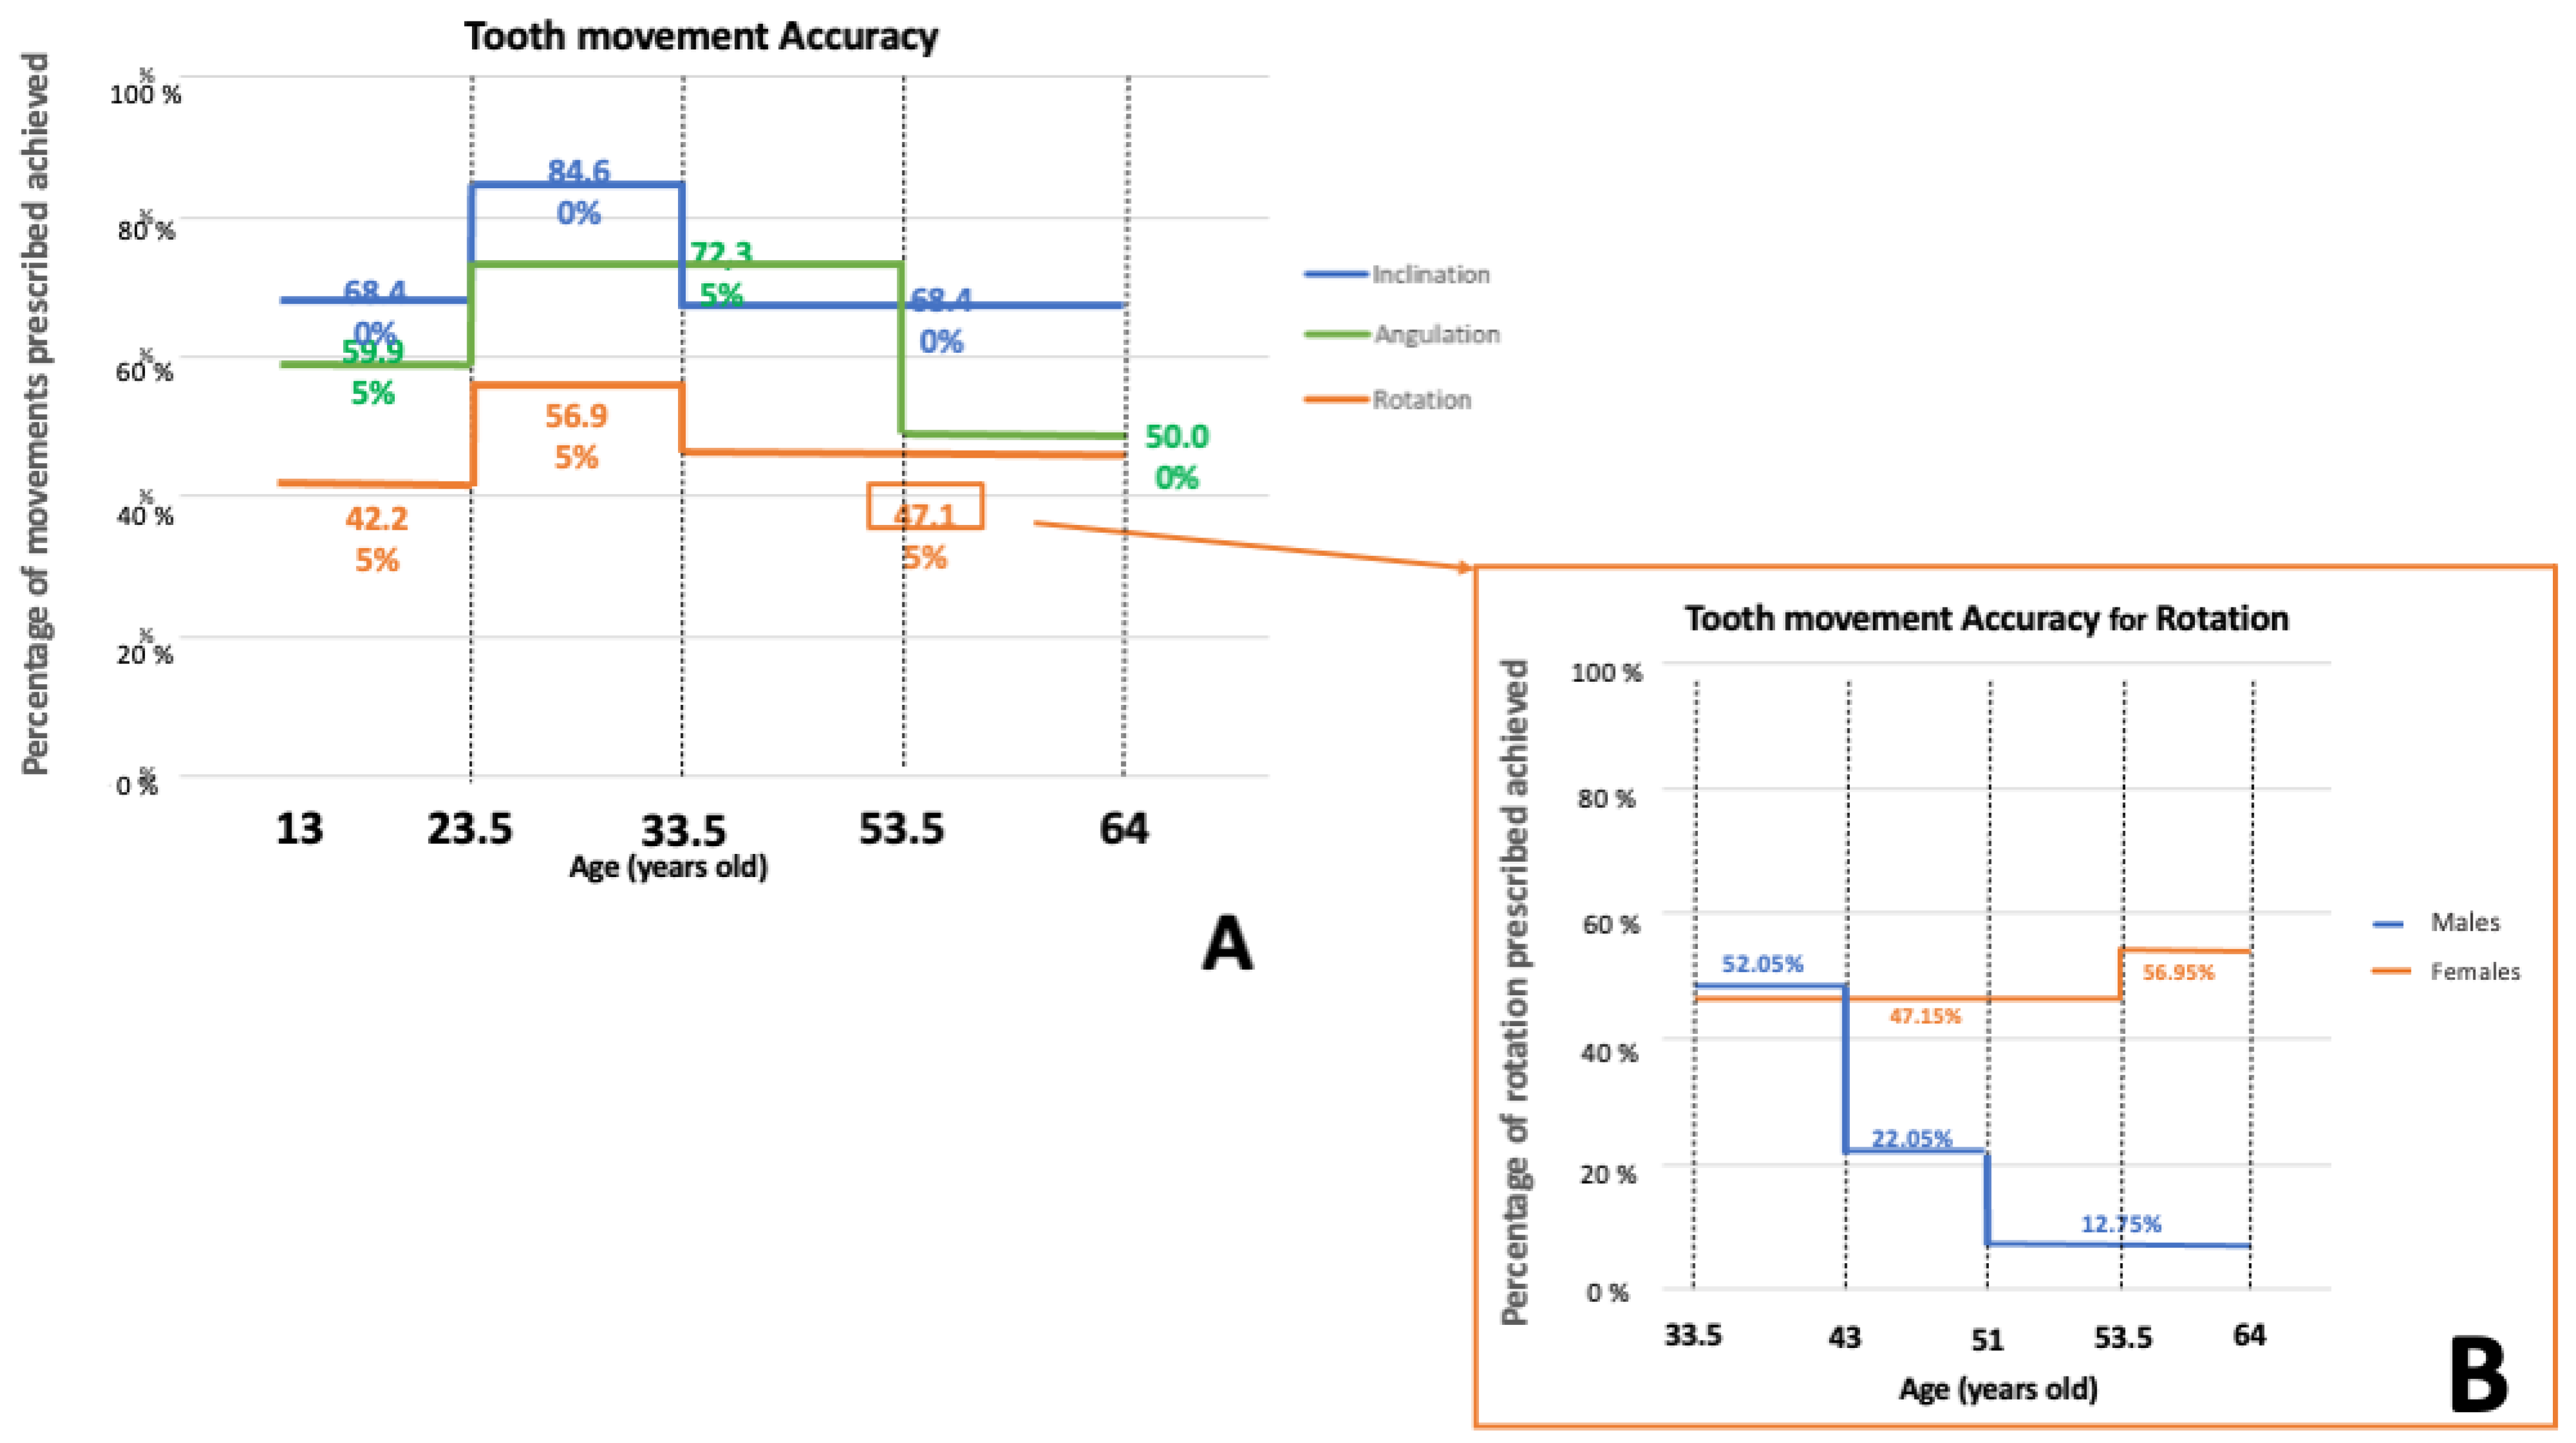

3. Results

- For all the movements investigated, the variables sex and age influence the percentage of movement achieved, which is greater in the intermediate age group (young adult patients). As for rotation, in the older group the trend seen in females (inverse relationship between accuracy and age) was reversed in males (direct relationship between accuracy and age).